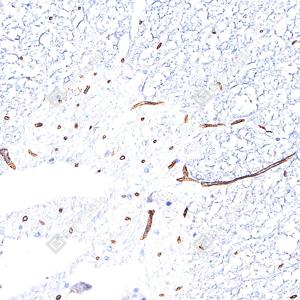

| IHC检测eNOS蛋白(货号 GB15086). 样品: 小鼠脾, 4%多聚甲醛 (货号G1101) 固定12-24小时. 抗原修复: 抗原修复仪(货号 ARI-4),Tris-EDTA抗原修复液(pH 9.0) (货号G1203), 水浴100℃, 25分钟. —抗: 1: 1000稀释, 4℃ 孵育过夜. 二抗: S-vision免疫组化多聚二抗(山羊抗兔),即用型 (货号G1302), 室温孵育20分钟. |